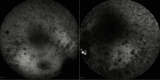

A case of a patient with the Alström syndrome (AS) that was misdiagnosed as Leber's hereditary optic neuropathy or retinitis pigmentosa for 13 years is presented. AS is a rare genetic disorder caused by mutations in the ALMS1 gene. AS may lead to abnormal ciliary formation and function. AS affects metabolism, and symptomatology includes type 2 diabetes mellitus (T2DM), obesity, hypogonadism and gynecomastia in males, progressive bilateral sensorineural hearing loss, cardiomyopathy, nonalcoholic fatty liver disease (NAFLD), cirrhosis, and chronic progressive kidney disease. The onset of the above symptoms may vary significantly. The ophthalmic manifestation is early onset cone-rod dystrophy that starts as progressive vision loss, photophobia, and nystagmus in the first months of life. An accurate diagnosis may enable specialists to facilitate a significantly positive effect in the everyday life of a patient. Genetic counseling may also be recommended for these patients. Diagnosis was confirmed by DNA testing, thus highlighting its necessity in everyday practice.